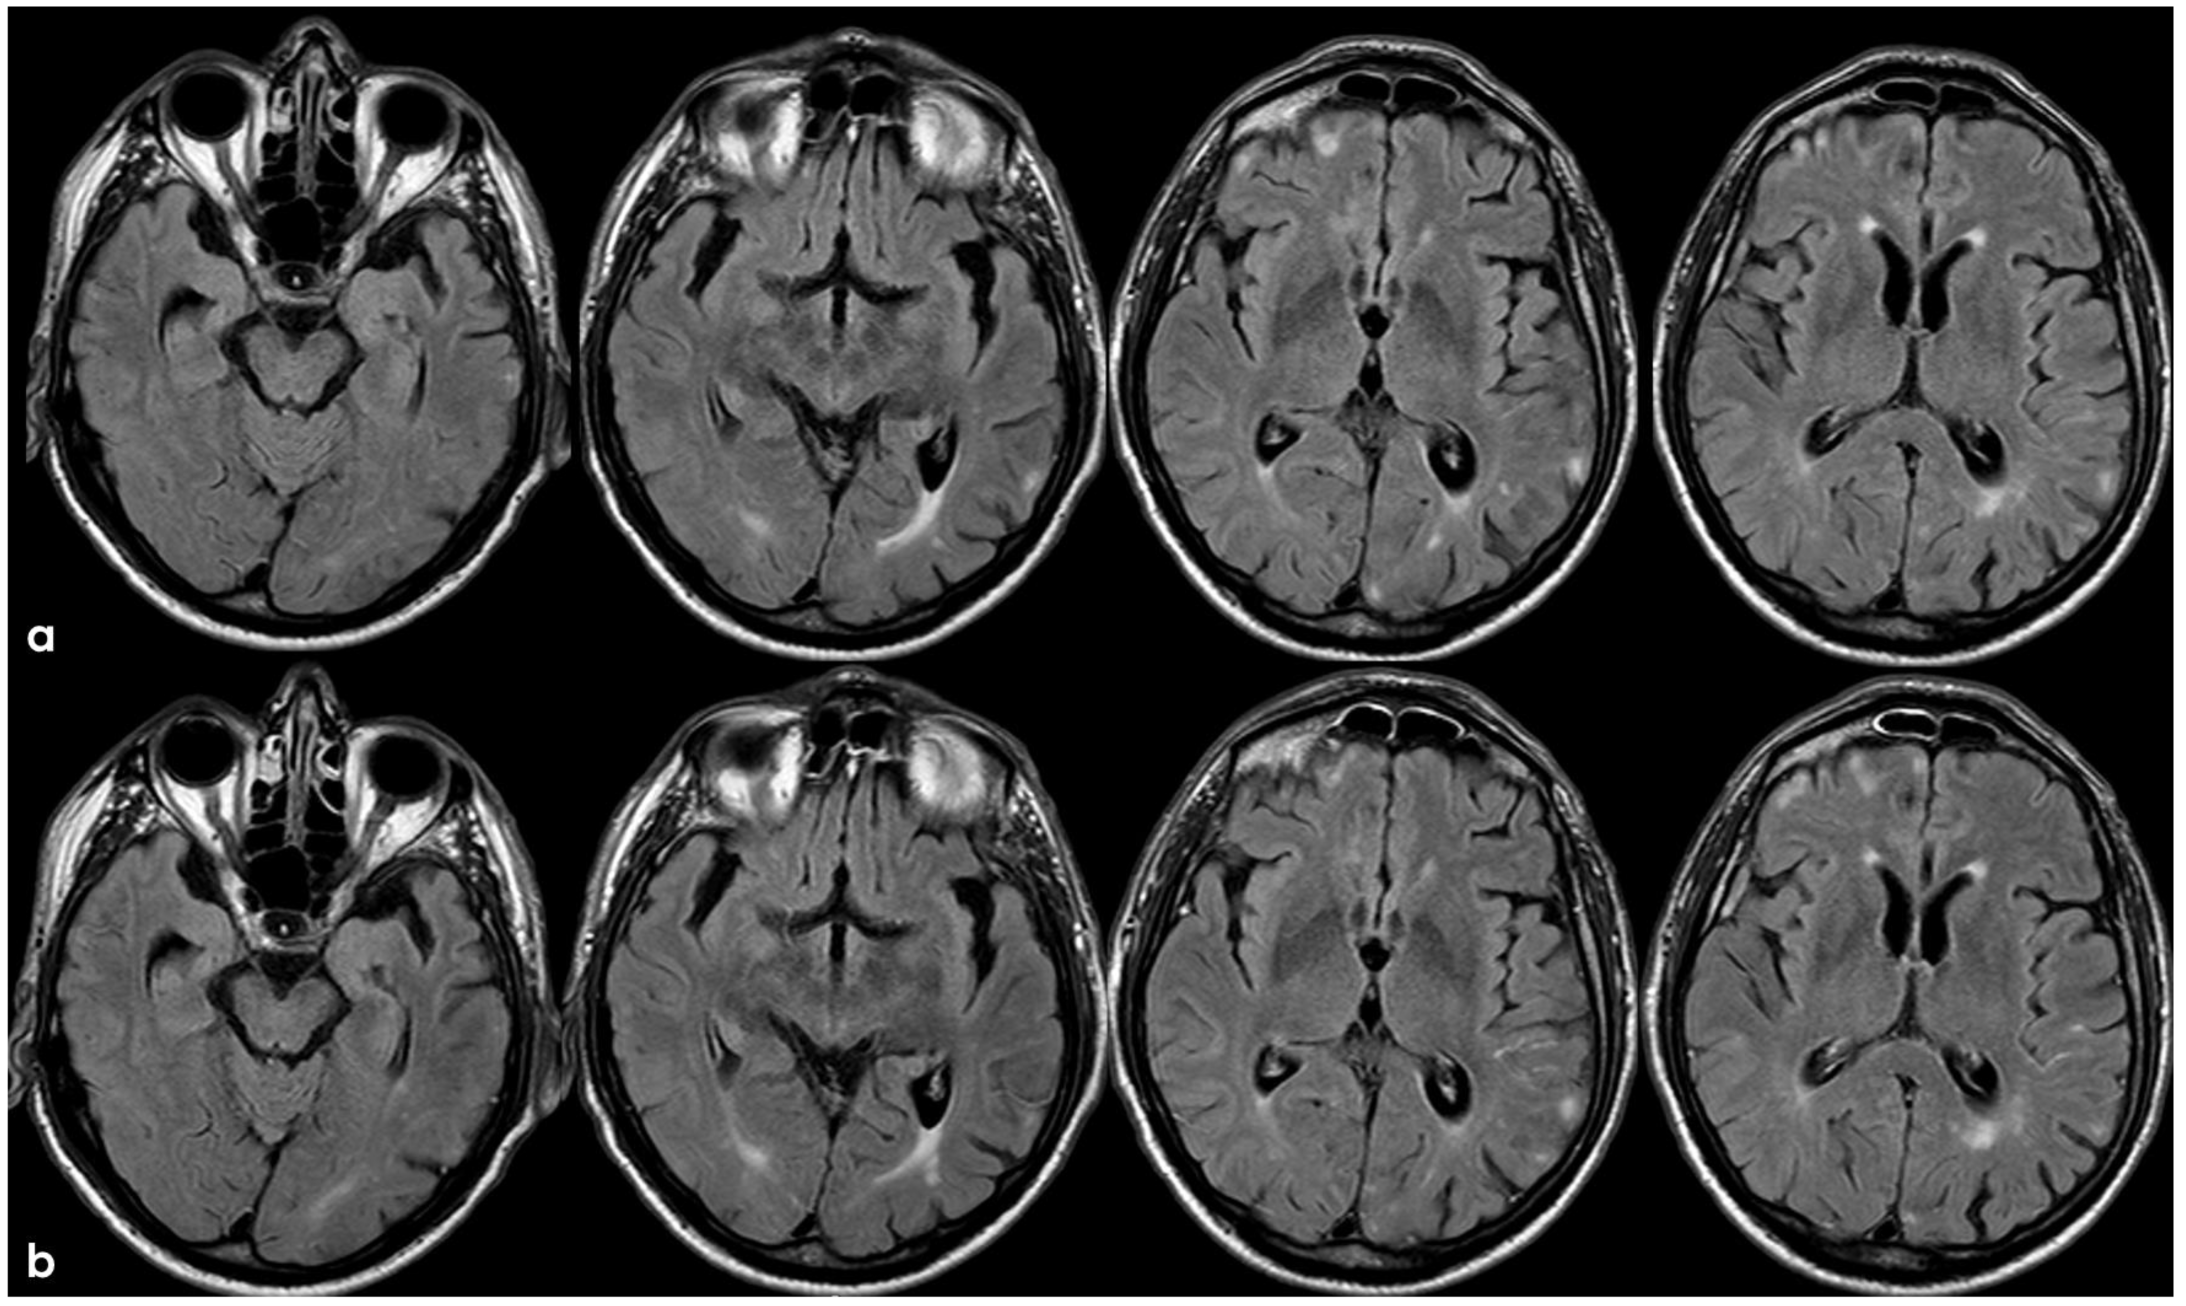

4. December 2015: Ischemic Stroke